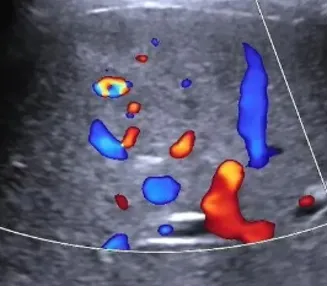

(3)CDFI:血流丰富,病灶可探测到一支血流由病灶外部进入病灶内(即滋养动脉),典型的呈轮辐状血流(但文献报道检出率低,仅20%可检出)。

● CDFI:大多数为富血供肿瘤。

肿瘤区域内有丰富的彩色血流信号。

高速、高阻。